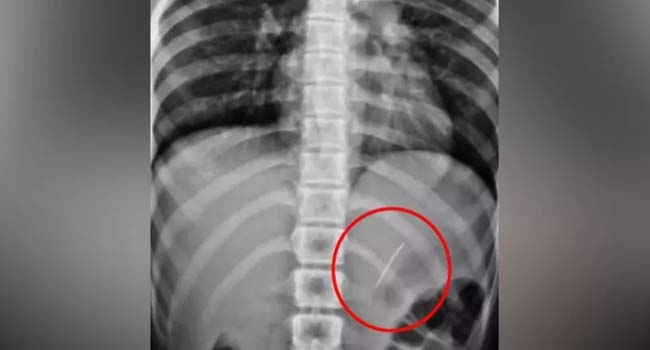

അവിടത്തെ എക്സ് റേ പരിശോധനയില് ആമാശയത്തില് പിന് തറച്ചതായി കണ്ടെത്തി. ഗ്യാസ്ട്രോ എന്ററോളജി വിഭാഗം മേധാവി ഡോ. സജു സേവ്യര്, ഗ്യാസ്ട്രോ എന്ററോളജിസ്റ്റ് ഡോ. ബിപിന്, ഡോ. സാജന് എന്നിവരുടെ നേതൃത്വത്തില് സര്ജറി കൂടാതെ എന്േറാസ്കോപിക് വഴി പിന് പുറത്തെടുക്കാനായി.